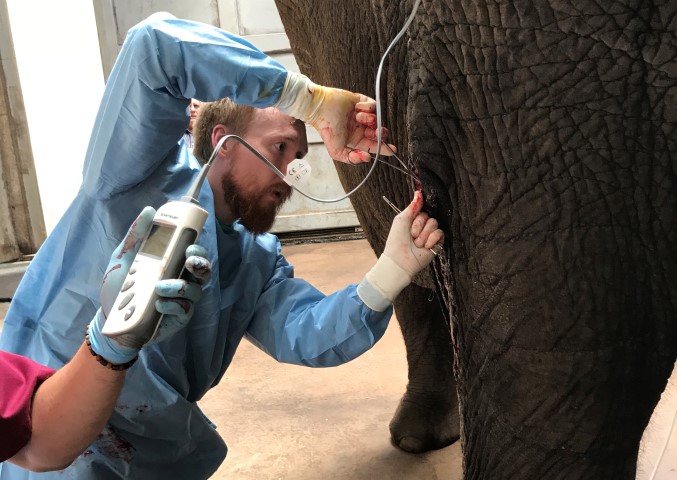

Local company helps the Earth’s most northern elephant

AdvertorialAccording to Wildilfe Pharmaceuticals, this fully reversible anaesthetic is the future as it reduces risk during any procedure.